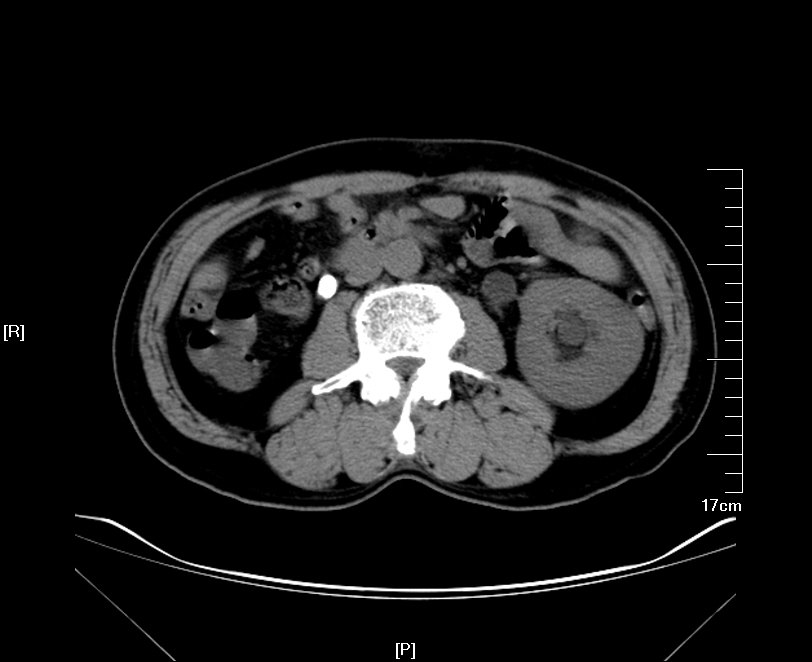

增强CT检查提示:右侧肾脏重度积水 皮质菲薄,右肾大部分实质已萎缩

KUB提示右输尿管上段结石,和右输尿管下段结石并存,如同河流上的两道堤坝,引起右输尿管完全梗阻,导致右肾萎缩

GFR:左侧37.9ml/min,右侧20ml/min,双侧肾脏功能均受损,右侧更为显著。